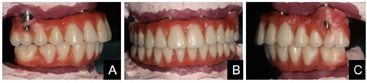

术后复查:术后3月全景片显示种植体骨结合良好(图7)。制作终义齿:术后5月:取下临时固定义齿,制取上下颌硅橡胶印模,根据临时义齿,记录上下颌颌位关系,上牙合架。术后6个月:制作义齿蜡型、排牙(图8),取下临时固定义齿,口内试戴上下颌终义齿蜡型,检查咬合关系良好,上下颌中线居中、对称,露齿线、唇颊面部丰满度患者满意。术后6个月:取下临时义齿,戴入终义齿,修复至第一磨牙(图9)。随访术后1年:全景片显示种植体周围骨结合良好,上前牙区种植体颈部骨吸收约1 mm(图10)。术后2年:义齿外形无变化,组织面有菌斑沉积。治疗计划:1.患者口腔卫生宣教,指导正确刷牙,采用冲牙器冲洗义齿与牙龈间缝隙,要求定期(6个月)复查、维护。2.取下上下颌义齿,复合基台周围洁治,清洁义齿,抛光义齿组织面,重新戴入固定上下颌义齿(图11)。术后2年全景片:种植修复前后面像对比(图13)。